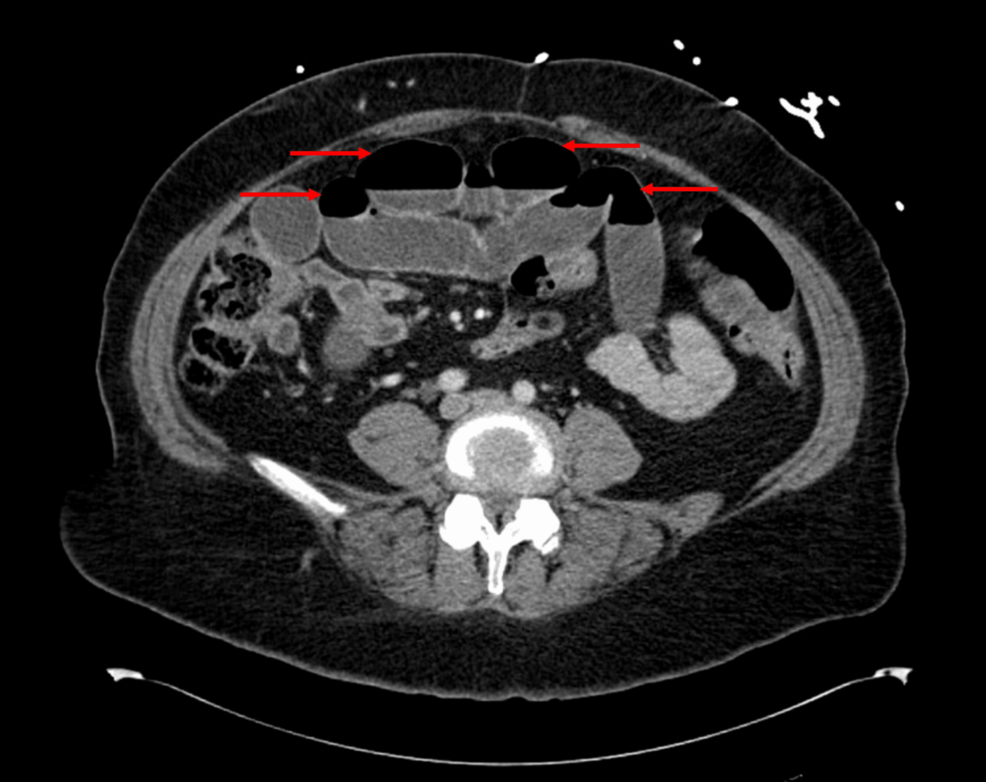

Severe Small-Bowel Obstruction in a High-Risk Patient on Long-Term Tirzepatide Therapy: A Case Report  Cureus